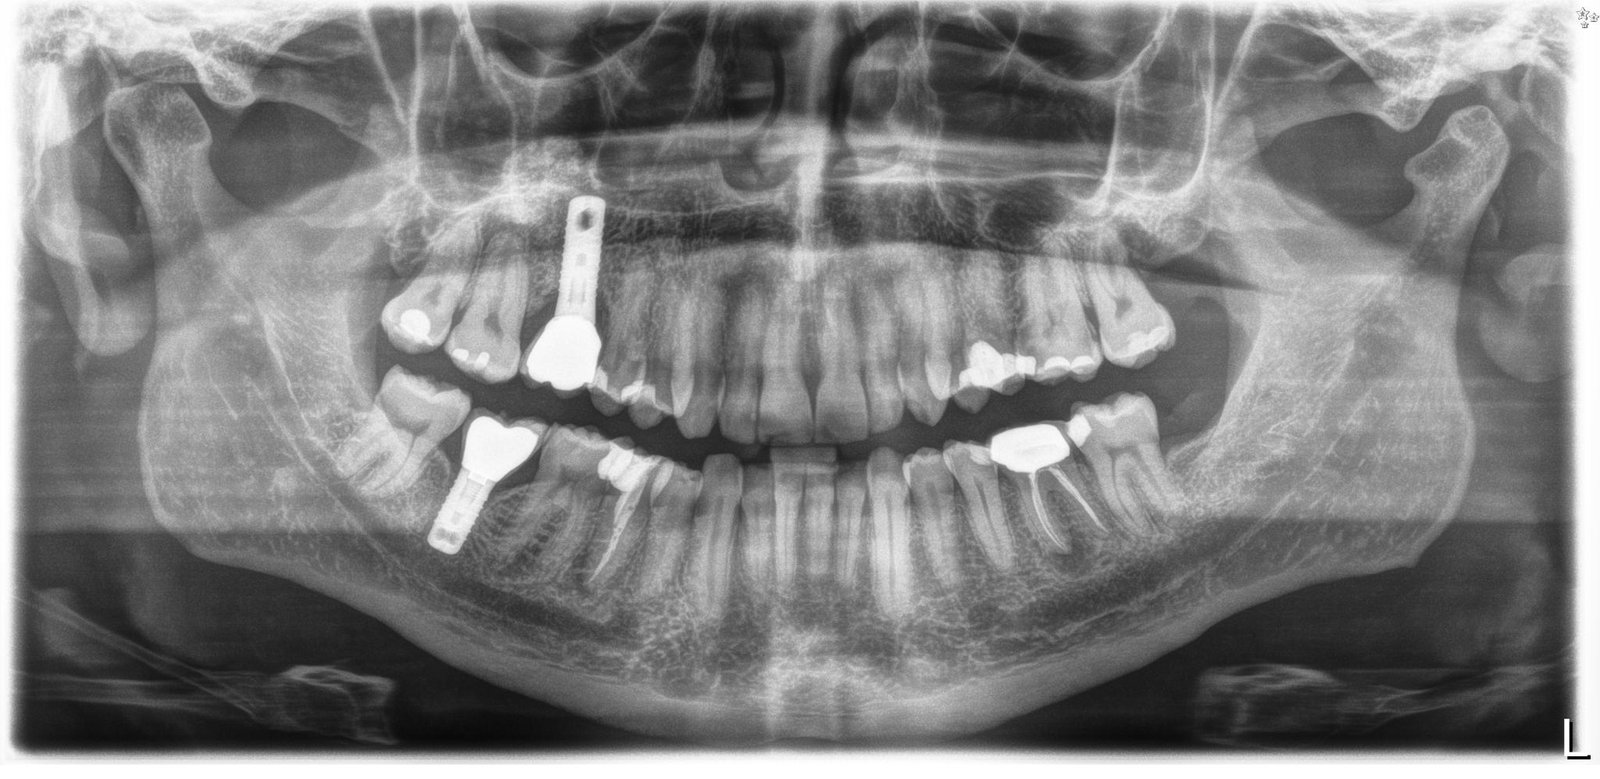

Buenas tardes, me podríais ayudar con la marca del implante? esta sacada de la orto , pero si no se ve claro puedo hacerle una periapical, muchas gracias de antemano